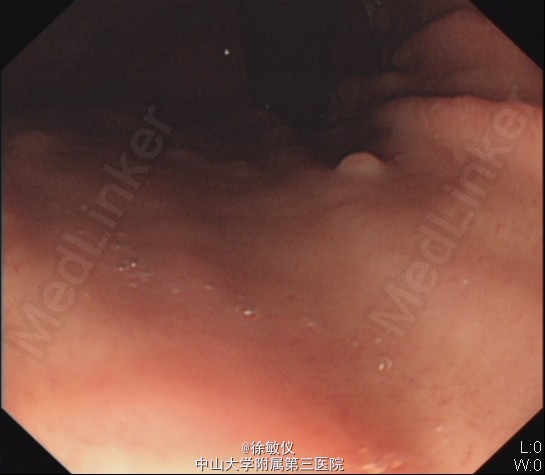

行胃镜检查,示1、胃多发息肉, 2.慢性浅表糜烂性胃窦炎。予行息肉钳除术。病理:(胃底、胃体息肉)胃底腺息肉。 予切除息肉后,予护胃调节植物神经功能等治疗,腹痛症状渐好转。